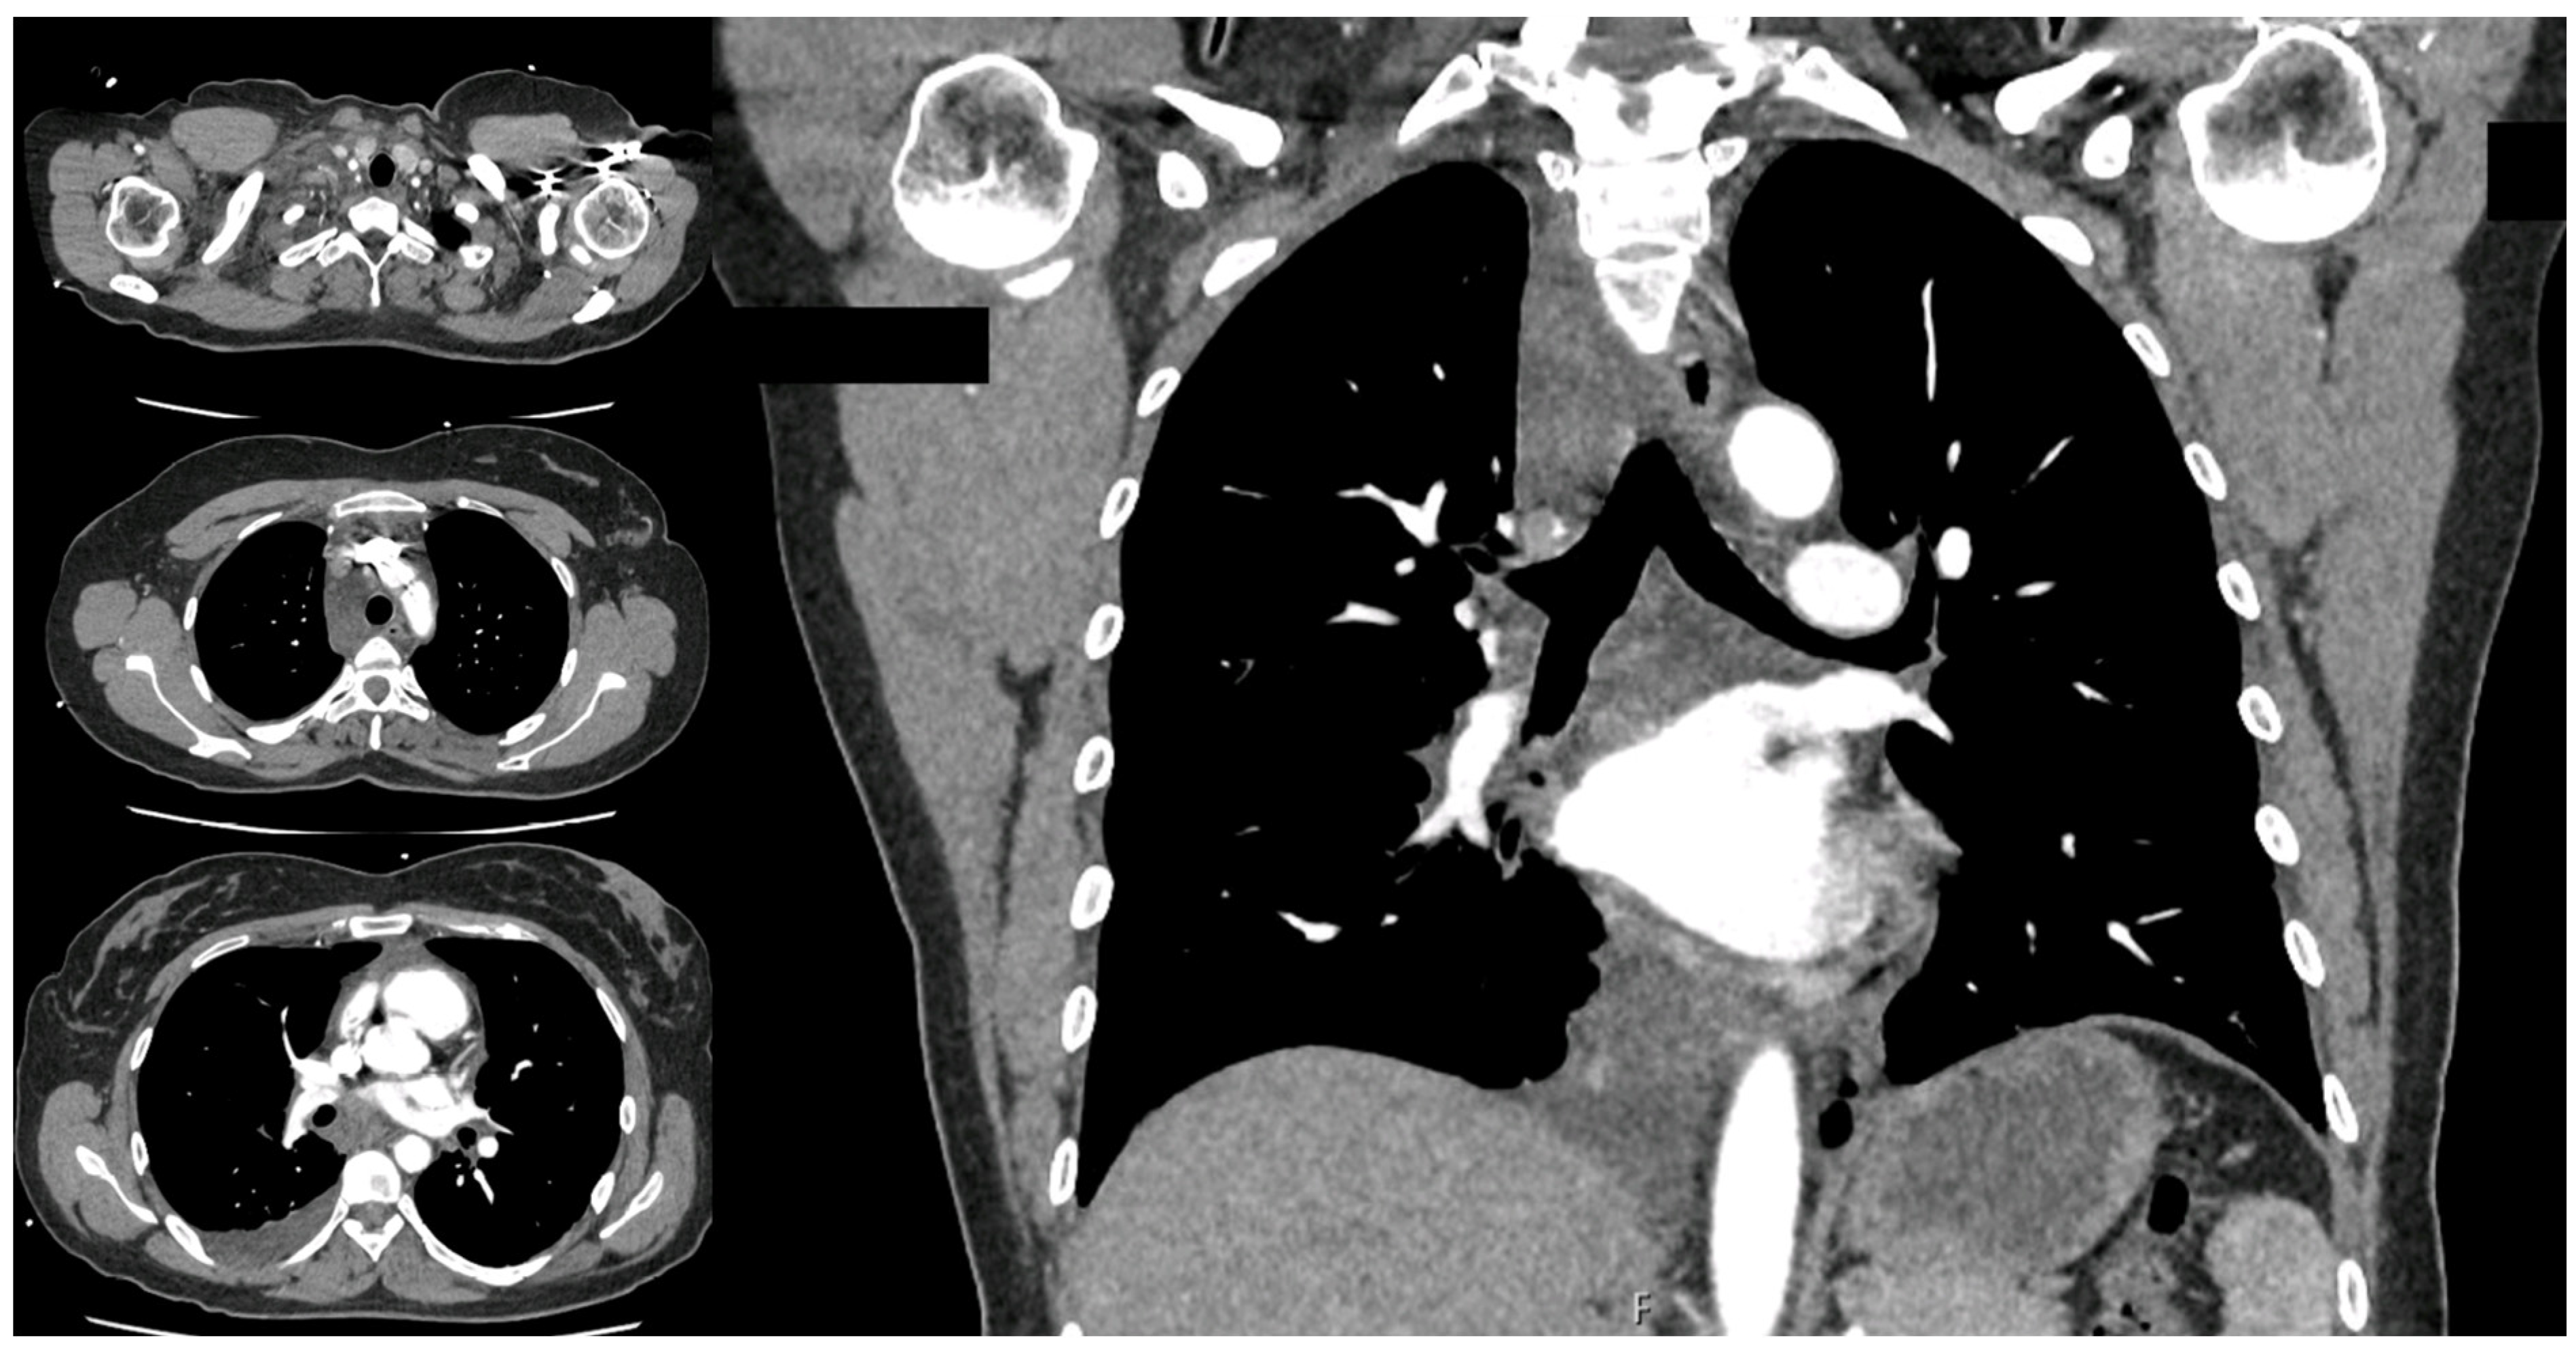

2. Case Presentation